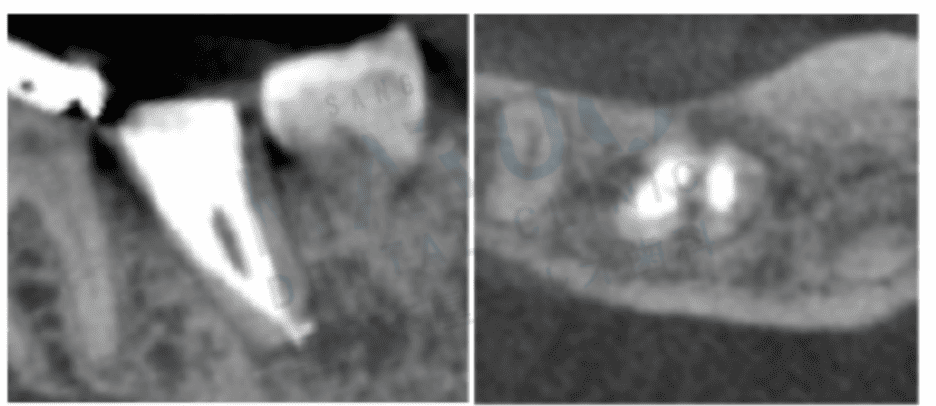

根の治療後に咬合痛がある

治療内容の詳細:

感染根管治療 (再根管治療) (大臼歯)

年齢・性別:50代・女性

費用:88,000円(税込)

治療にかかる期間や回数:4~5回 (治療期間は1~2ヶ月、予後観察1年)

主なリスク:根が割れている場合は保存が困難

副作用:治療後に治療による痛みが生じることがあります。

根管治療の成功は、単に痛みを取るだけでなく、再発リスクを抑えながら歯を長期的に残すことにあります。当院がこれまでに担当してきた症例の多くで、適切なメンテナンスを継続することで、治療後も問題なく使い続けられている患者さんが多数いらっしゃるのは、大きな励みとなっています。